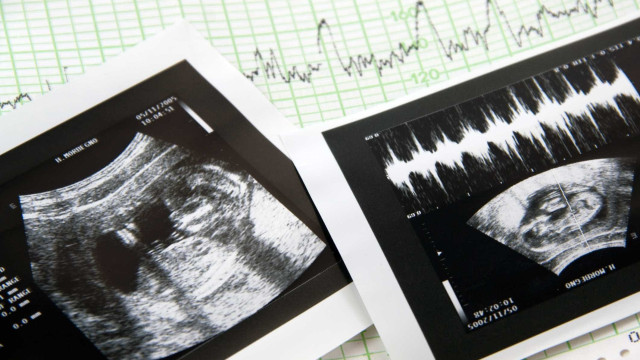

The General Inspectorate of Health Activities (IGAS) has initiated an inspection process at the Ceraque clinic in Pinhal Novo, which allegedly failed to detect a severe malformation in a fetus during a morphological ultrasound, a procedure intended to assess the anatomy of the baby.

Throughout the pregnancy, including the morphological ultrasound conducted at this clinic, the parents were told that there were no issues with their child. It was only at the birth of the child that the parents discovered the baby had an incomplete right leg and only two toes on one foot.